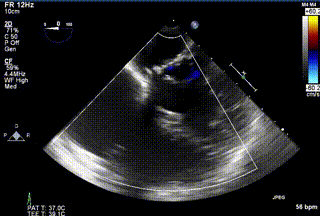

2021年12月24日,復旦大學附屬中山醫院葛均波院士團隊成功應用LuX-Valve Plus為一例極重度三尖瓣反流(TR)合并房顫、房缺的患者完成了經血管三尖瓣置換術,這是在前基礎上,本周完成的第三例經血管三尖瓣置換手術,葛均波院士、周達新教授等與心外科魏來教授、賴顥教授,心超室的潘翠珍教授、李偉教授及麻醉科的郭克芳教授共同完成了本周手術,均獲得圓滿成功!患者術后超聲顯示無TR,臨床癥狀明顯改善。本周手術的成功也為LuX-Valve Plus救治性臨床研究添上了濃墨重彩的一筆。

三例患者入院后,葛均波院士團隊周達新教授、潘文志教授、張源博士、陳莎莎博士及心超室的潘翠珍教授、李偉教授對患者的情況進行詳細評估和討論,最終決定為三例患者選擇LuX-Valve Plus40mm、50mm和50mm型號的瓣膜進行手術治療。手術后即刻拔除氣管插管,術后患者三尖瓣反流癥狀得到顯著改善,復查心超結果顯示人工三尖瓣瓣膜支架固定穩定,瓣葉關閉形態未見異常,未見明顯反流。